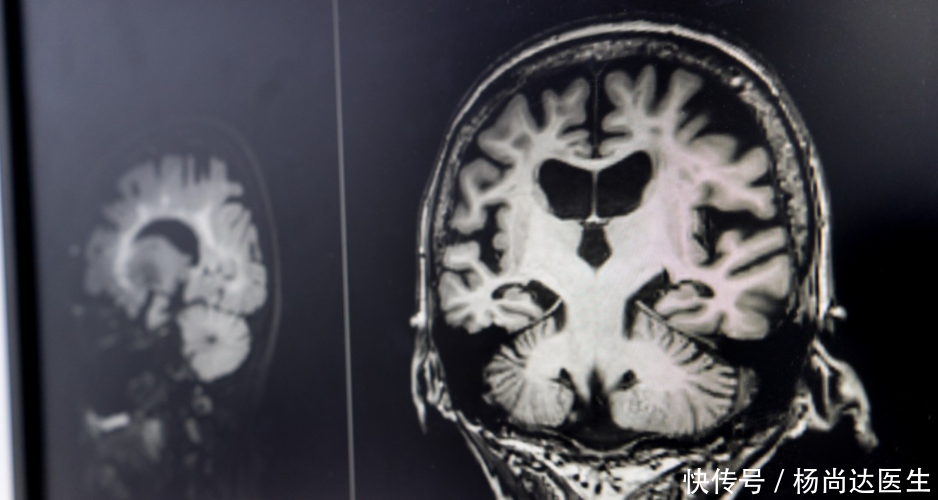

为什么脑梗者男性更多?专家提醒:出现7种症状马上就医